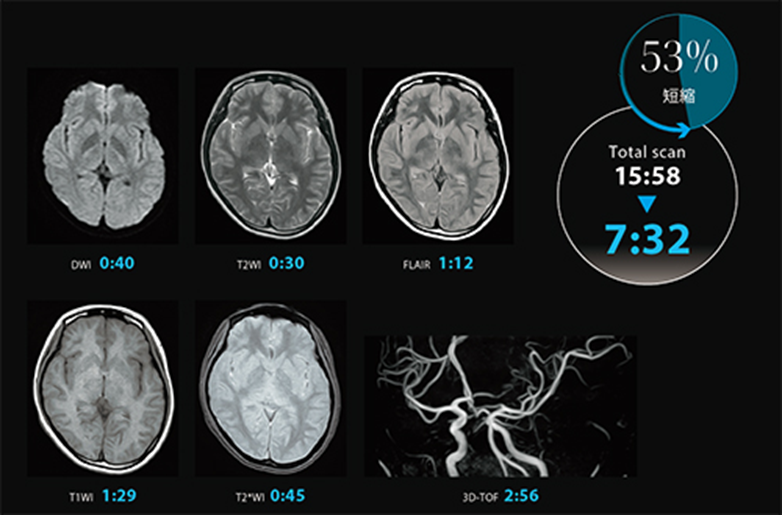

- Express: Tăng tốc quét nhờ công nghệ AiCE, Exsper, SPEEDER và Fast 3D – giúp rút ngắn thời gian xét nghiệm đến 50%